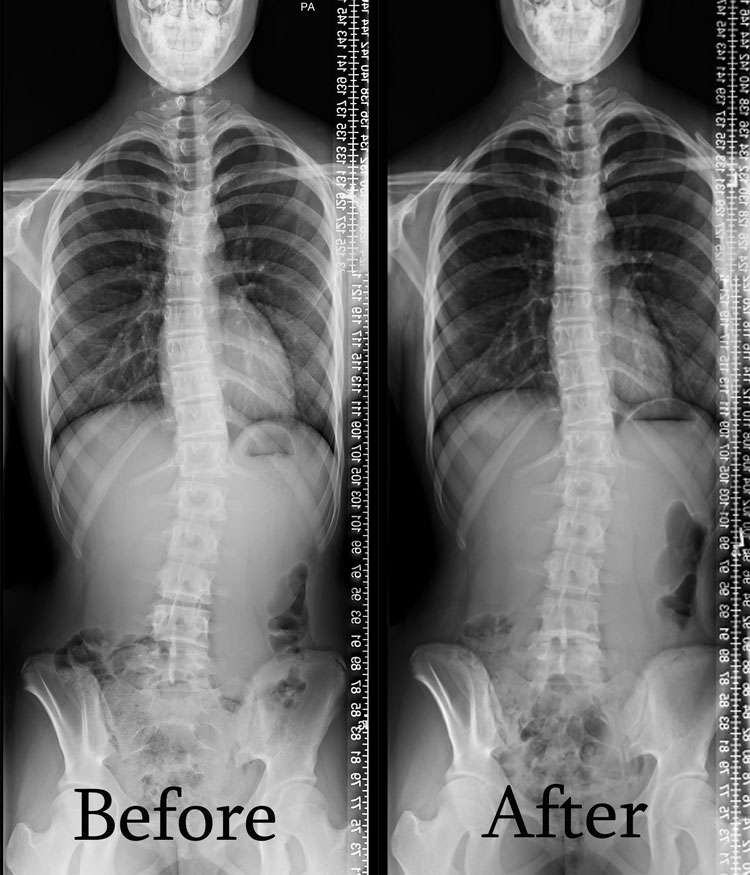

Scoliosis is measured on x-ray as a Cobb Angle. This measurement tells us how bad the scoliosis is and then guides us in how we treat it. Curves under 10 degrees usually aren’t considered scoliosis. Those curves 10-25 are called mild curves and we treat them with scoliosis specific exercise. Curves 25-45 degrees are treated with scoliosis specific exercise and bracing. Those above 45 degrees are usually surgical candidates. There is a measurement error of 3-5 degrees, which means to really have significant change, it needs to be above that.

Here are some examples of what can be done with scoliosis specific exercise with a variety of patients. The main goal of treatment is to STOP progression of the curve. With hard work and dedication we can also see reduction in the curve.